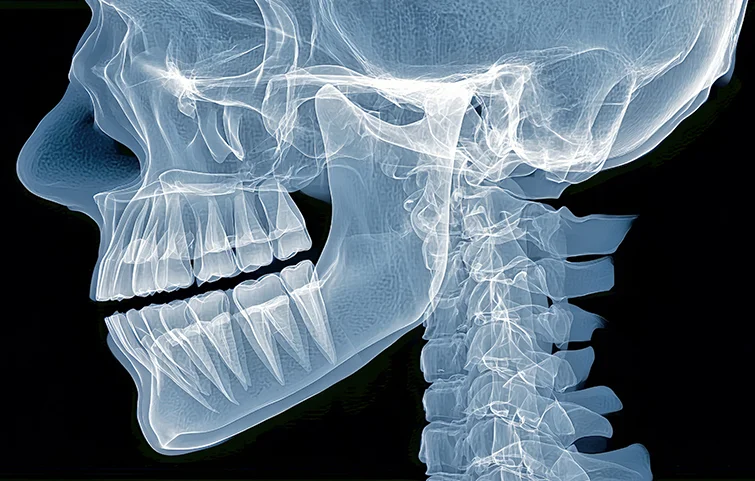

Jaw fractures are breaks in the jawbone, commonly affecting the mandible (lower jaw) or the maxilla (upper jaw). They can result from trauma, such as falls, sports injuries, or accidents, and can lead to significant functional and aesthetic issues if not properly treated.

Jaw fractures, particularly of the mandible or maxilla, are commonly caused by trauma from accidents, sports injuries, or violence. Diagnosis begins with a thorough clinical evaluation. The patient may present with facial swelling, bruising, pain, difficulty in opening or closing the mouth, malocclusion (improper bite), and numbness due to nerve involvement.

Physical examination includes assessing jaw alignment, mobility, and palpation for stepoffs or crepitus. Intraoral examination checks for bleeding, lacerations, or tooth mobility. Imaging is crucial for confirmation. A panoramic X-ray (orthopantomogram) is a common initial tool to visualize the mandible. However, computed tomography (CT) scans are the gold standard for complex fractures or midface injuries, providing detailed 3D visualization of bone involvement.

In some cases, cone-beam CT (CBCT) may be used, especially in dental settings, to assess smaller or localized fractures. If the fracture involves the condyle or temporomandibular joint, additional TMJ-specific views may be needed. Associated injuries such as dental fractures or airway compromise should also be evaluated.

Treatment decisions are guided by imaging findings, location of the fracture (e.g., angle, symphysis, condyle), displacement, and patient symptoms. The goal of diagnosis is not only to confirm the fracture but also to assess complications, such as infection, nerve damage, or airway obstruction, ensuring timely and appropriate surgical or non-surgical intervention.